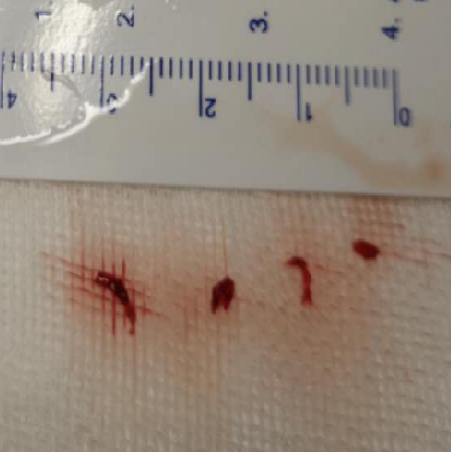

2、SWIM操作:0.014”微导丝+Rebar 18微导管通过LMCA M1段,手推造影剂示真腔,撤出微导丝,通过微导管将Solitaire 6-30支架输送至M1段,缓慢释放支架,远端在M1中段,近端在床突段,造影可见左侧前向血流部分恢复,眼动脉显影良好,眼动脉段可见充盈缺损。等待5分钟,推送React™ 68导管至支架近段,负压抽吸并缓慢回撤支架,然后撤出导管。可见支架体附着质软红色血栓,导管内抽出大量细碎的栓子。

本例患者,既往无明显内科疾病,常年吸烟史,通过造影可见,左侧颈内动脉眼动脉段重度狭窄,和前交通代偿血流形成对抗血流,当血栓形成并进一步加重时,狭窄处的前向血流减弱,进而狭窄的近端和远端不断形成血栓。患者症状在静脉溶栓时出现症状的减轻后再加重的波动,可能也与远端栓子脱落有关,尽早开通病灶侧的血管仍是必要的。取出的栓子质地较软、新鲜,考虑以红血栓为主,也印证这点。